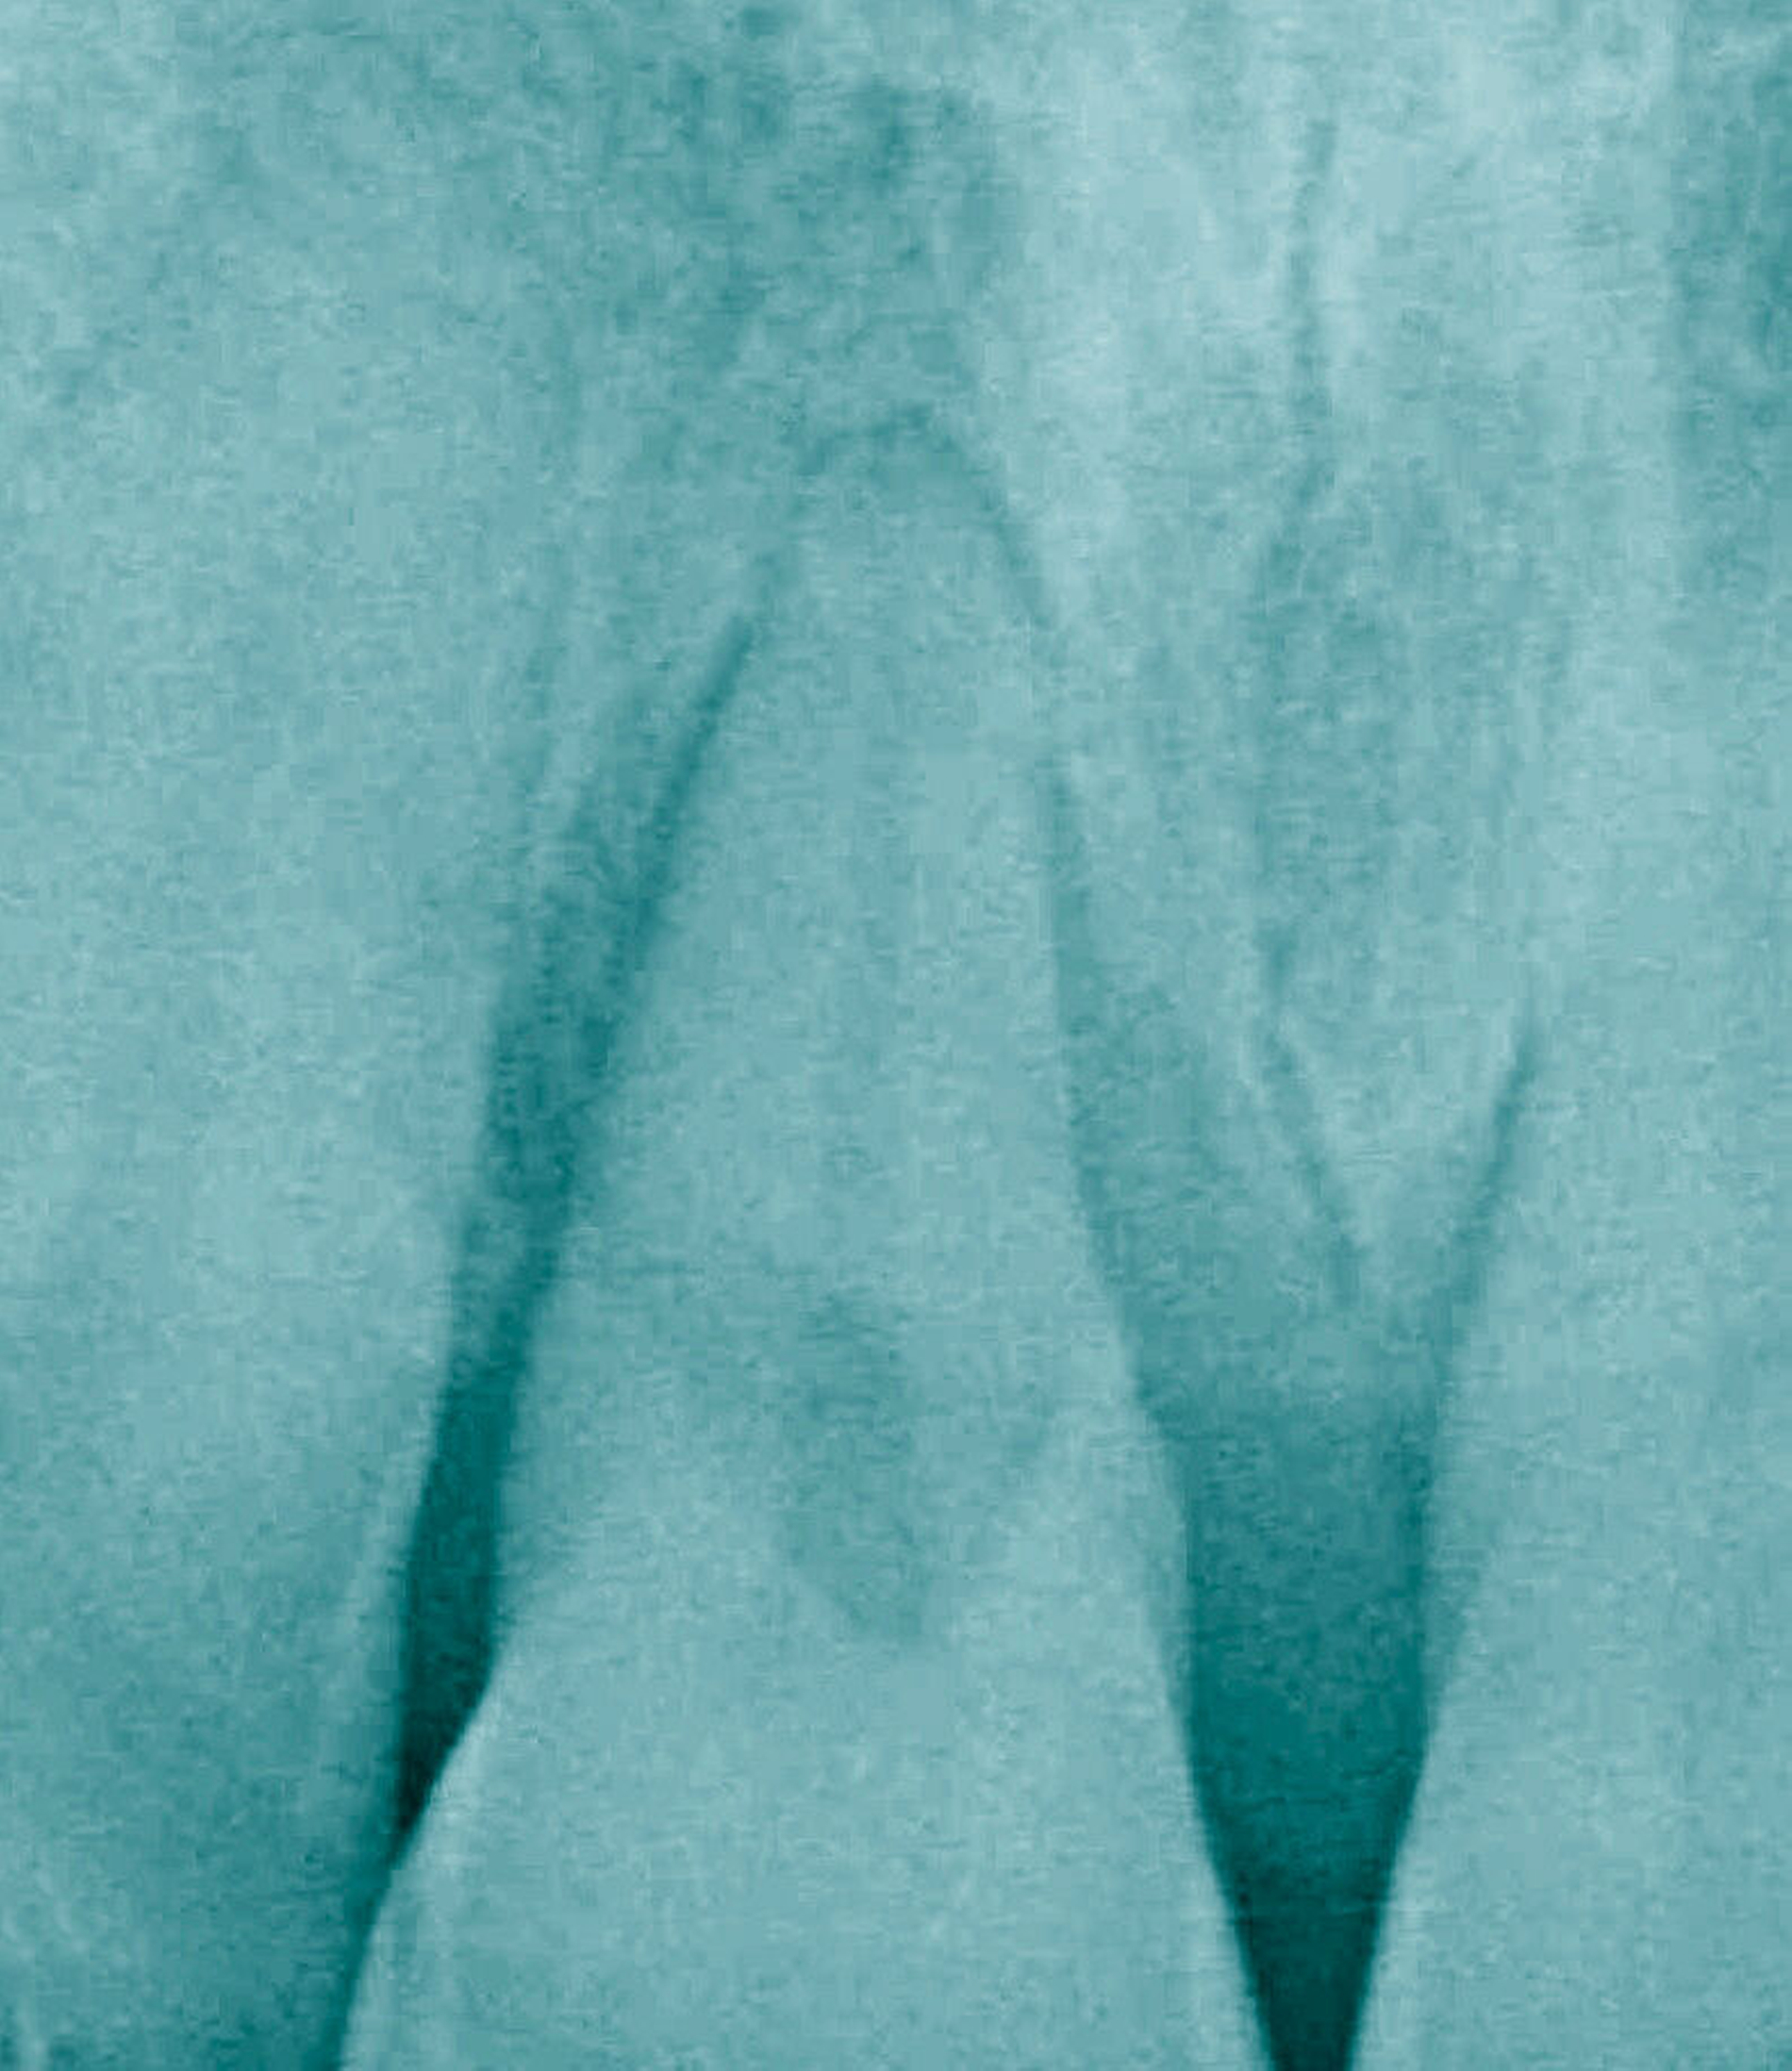

Bei einer Heilung per primam sind die Wundränder glatt, gut durchblutet, spannungsfrei aneinander liegend und präzise adaptiert. In der initialen, hämostatischen Phase bildet sich ein dünnes Blutgerinnsel zwischen den Wundrändern. Die Anhaftung dieses Koagulums fungiert als Abwehr gegenüber mechanischen Belastungen auf die präparierten Lappen [Wikesjö et al., 1991]. Blutplättchen geben Wachstumsfaktoren ab, die die Heilung einleiten. Es bildet sich eine Matrix aus weißen Blutkörperchen, die die Wunde bedeckt. Es kommt zu einer leichten Entzündungsreaktion, in deren Folge meist keine Gewebeschädigung verursacht wird. Die Gefahr einer bakteriellen Infiltration wird durch den Verschluss im oberflächlichen Bereich der Wunde nahezu vollständig vermieden [Cortellini & Tonetti, 2009]. Die Bildung von Narben- oder Granulationsgewebe wird minimiert, eine vollständige Ausheilung der Wundregion und eine Wiederherstellung der Gewebe ermöglicht (Abbildung 1).

Im Gegensatz dazu erfolgt die Wundheilung bei nicht primär verschlossenen beziehungsweise aufgrund eines Gewebedefekts nicht primär zu verschließenden Wundrändern sekundär unter Ausbildung von Reparationsgewebe. Um eine solche Wunde rasch zu schließen und die Integrität der epithelialen Auskleidung der Mundhöhle schnell wiederherzustellen, überbrückt der Körper hierbei den zerstörten oder fehlenden Gewebeanteil durch minderwertiges Narbengewebe. Häufig verursachen nach dem Nahtverschluss zu starke auf die Lappen einwirkende Zugkräfte, nicht präzise geknüpfte und sich deshalb lösende Nähte oder auch durch eine lokale Minderdurchblutung der Gewebe hervorgerufene Nekrosen der Wundränder den sekundären Wundheilungsverlauf einer zunächst primär verschlossenen Wunde. Das Behandlungsergebnis ist oftmals durch Wunddehiszenzen, Lappenretraktionen, hypertrophe Narben, fibrotisches Gewebe und Volumendefekte beeinträchtigt [Bhattacharya et al., 2014; Wikesjö & Nilvéus, 1990] (Abbildung 2).